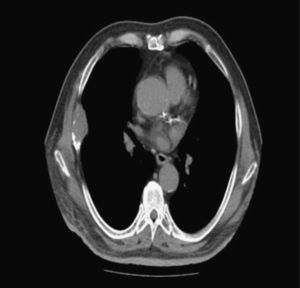

A 67-year-old male, non-smoker, a native of Ağrı (Eastern Anatolia), was admitted to our clinic with a 3-month history of cough and loss of appetite. Physical examination showed diminished breath sounds. Laboratory findings were within normal limits. Chest X-ray revealed a homogenous density adjacent to the right chest wall. Chest computed tomography (CT) showed a 52×28mm extrapleural mass in the thoracic wall destroying the anterior right sixth rib (Fig. 1). Suspecting thoracic wall malignancy, transthoracic fine needle aspiration biopsy (TTFNAB) was performed. The cytology report indicated “homogenous eosinophyllic lamellar material of a hydatid cyst closely surrounded by scolices”. The patient underwent surgery to remove the cyst. Postoperative 15–20mg/kg/day albendazol treatment was initiated and finalized at 12 weeks. After 2 years of follow-up, the patient has not shown any sign of recurrence.

Hydatid cyst disease is usually asymptomatic, and is diagnosed after combined clinical, radiological, and specific laboratory tests.4 The metastasis of hydatid cyst in costa is generally slow, and laboratory tests are usually negative. In our case, specific laboratory studies for hydatid cyst were not performed, since thoracic wall tumor (osteosarcoma) was strongly suspected on the CT image of rib destruction, and TTFNAB was used to establish definitive diagnosis, even though guidelines recommend avoiding this technique in order to prevent tumor spread and minor or major allergic reactions.